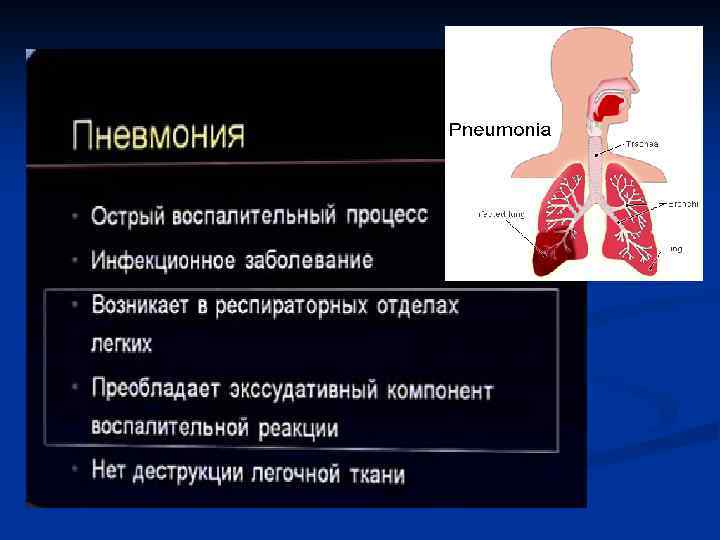

Респираторный отдел - совокупность анатомических структур легкого, расположенных дистальнее терминальных бронхиол и принимающих непосредственное участие в газообмене - респираторные бронхиолы - альвеолярные мешки - альвеолярные ходы - альвеолы - интерстициальные структуры